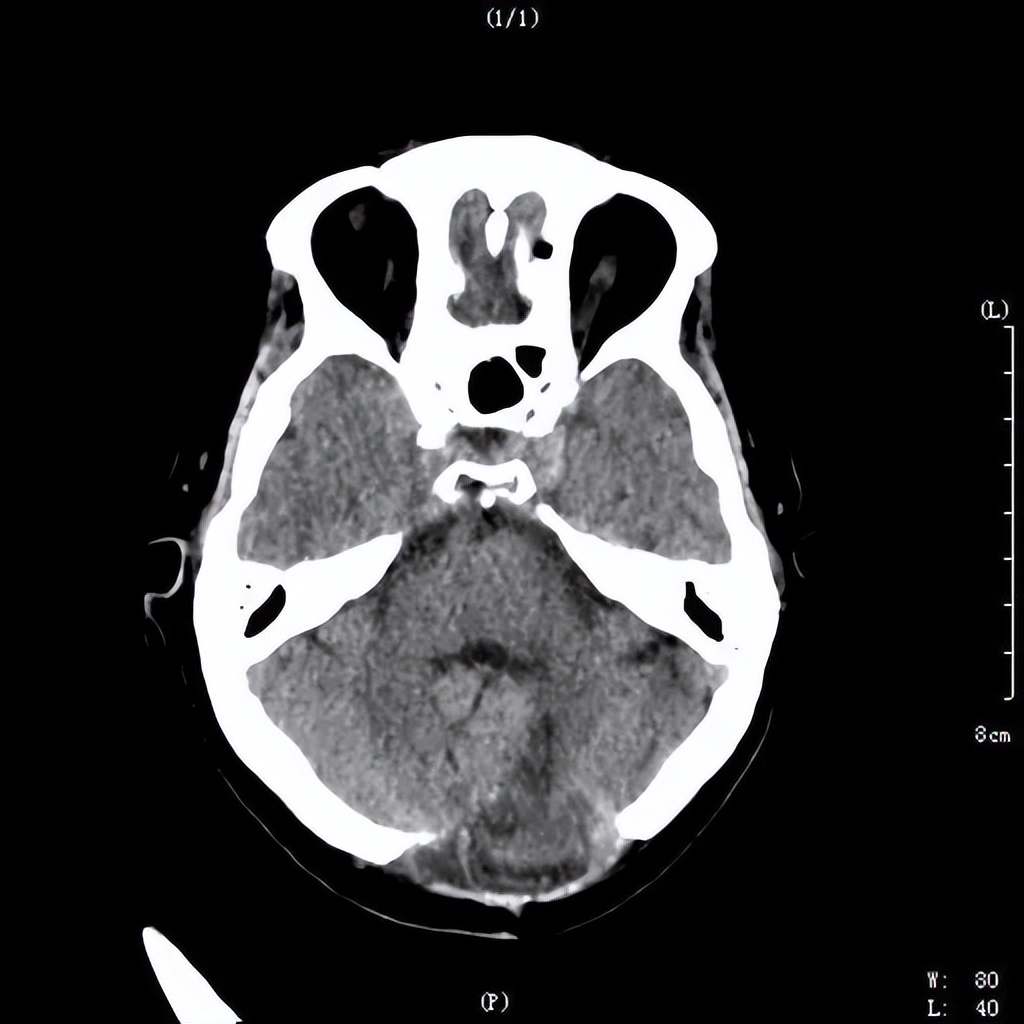

手术后血肿完全清除

出院前影像检查